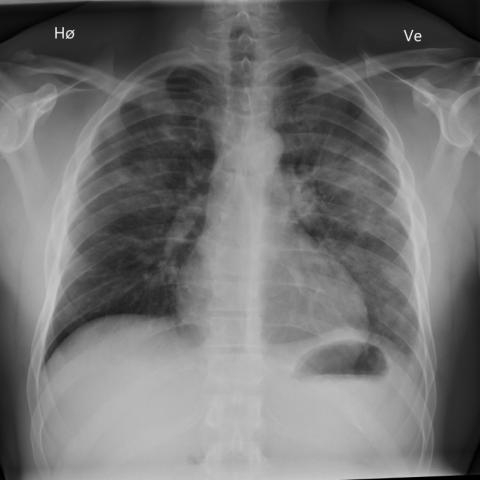

初次胸部 X 光检查显示双侧弥漫性肺泡浸润病变,提示肺炎。